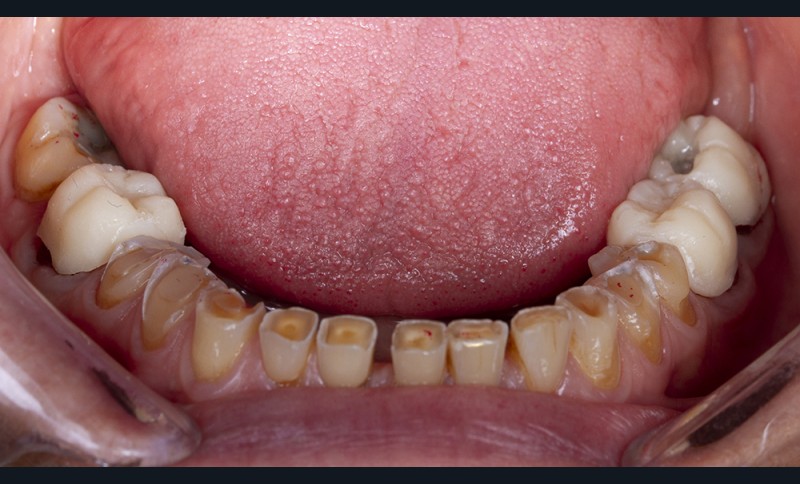

Le calage postérieur obtenu assure l’augmentation de la DVO et entraîne très souvent une béance antérieure avec une perte du guidage antérieur (fig. 8). Le traitement du groupe incisivo-canin est alors nécessaire.